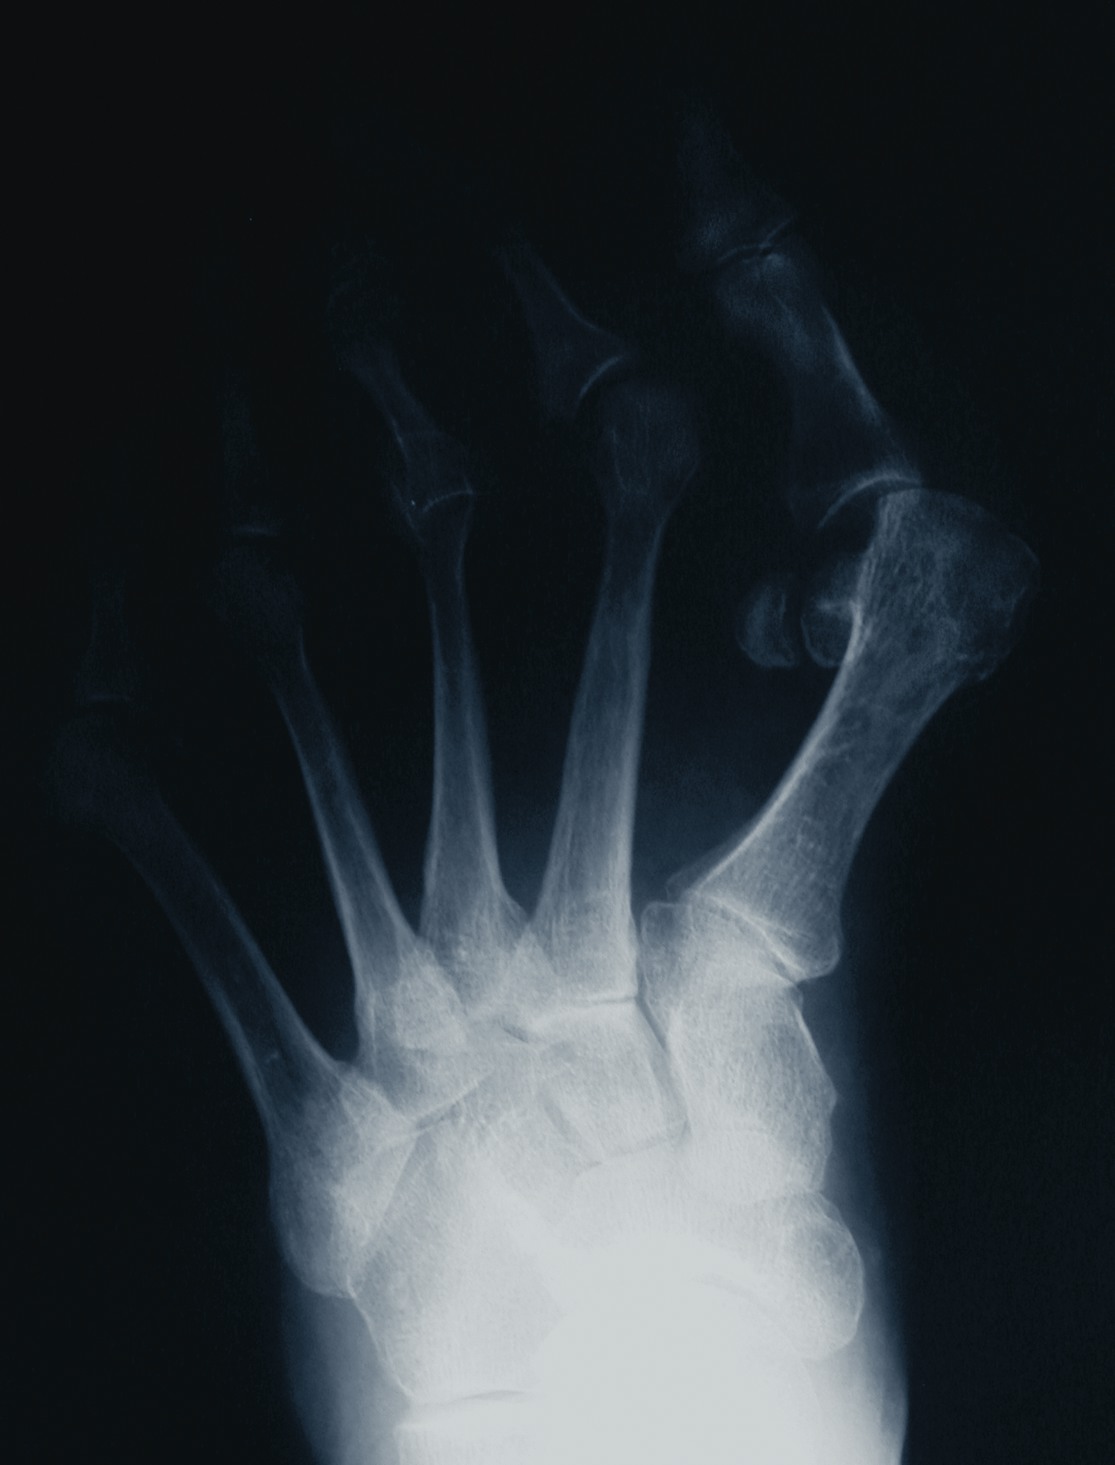

A Guide To Radiographic Findings Of First Ray Insufficiency

Several radiographic findings have been thought to be associated with hypermobility. These include first MCJ obliquity, cortical thickening of the second metatarsal shaft, diastasis of the first intercuneiform joint articulation and a short first metatarsal. According to Morton’s theory, a short metatarsal in relation to the second metatarsal transfers weight laterally. The obliquity of the first MCJ is thought to be an atavistic trait. Obliquity greater than 30 degrees has been considered abnormal and an indication for a first MCJ arthrodesis.15 However, radiographic studies have illustrated that this obliquity may be radiographically exacerbated.6,17 Diastasis between medial cuneiform and second metatarsal base and/or diastasis of the first intercuneiform joint may suggest the presence of hypermobility in a location other than the first MCJ. One should be careful to notice radiographically exacerbated widening as well. Morton considered hypertrophy of the second metatarsal shaft the physiologic response to increased load secondary to first ray hypermobility. Some surgeons have also supported this association while others dispute it.18-22 Coughlin and Grebing found no association between first ray mobility and second metatarsal cortical hypertrophy in 43 patients with hallux valgus compared to a control group.22 Although patients with hypermobility were not specifically compared to the controls, the mean mobility of the first ray was 6.9 mm (ranging from 3 mm to 12 mm).